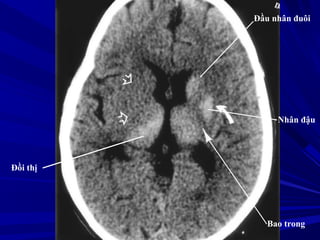

Nhân đậu

Cánh tay sau

bao trong

Đồi thị

Sừng trán não

thất bên

Nhân đuôi

Vách trong suốt

Đầu nhân đuôi